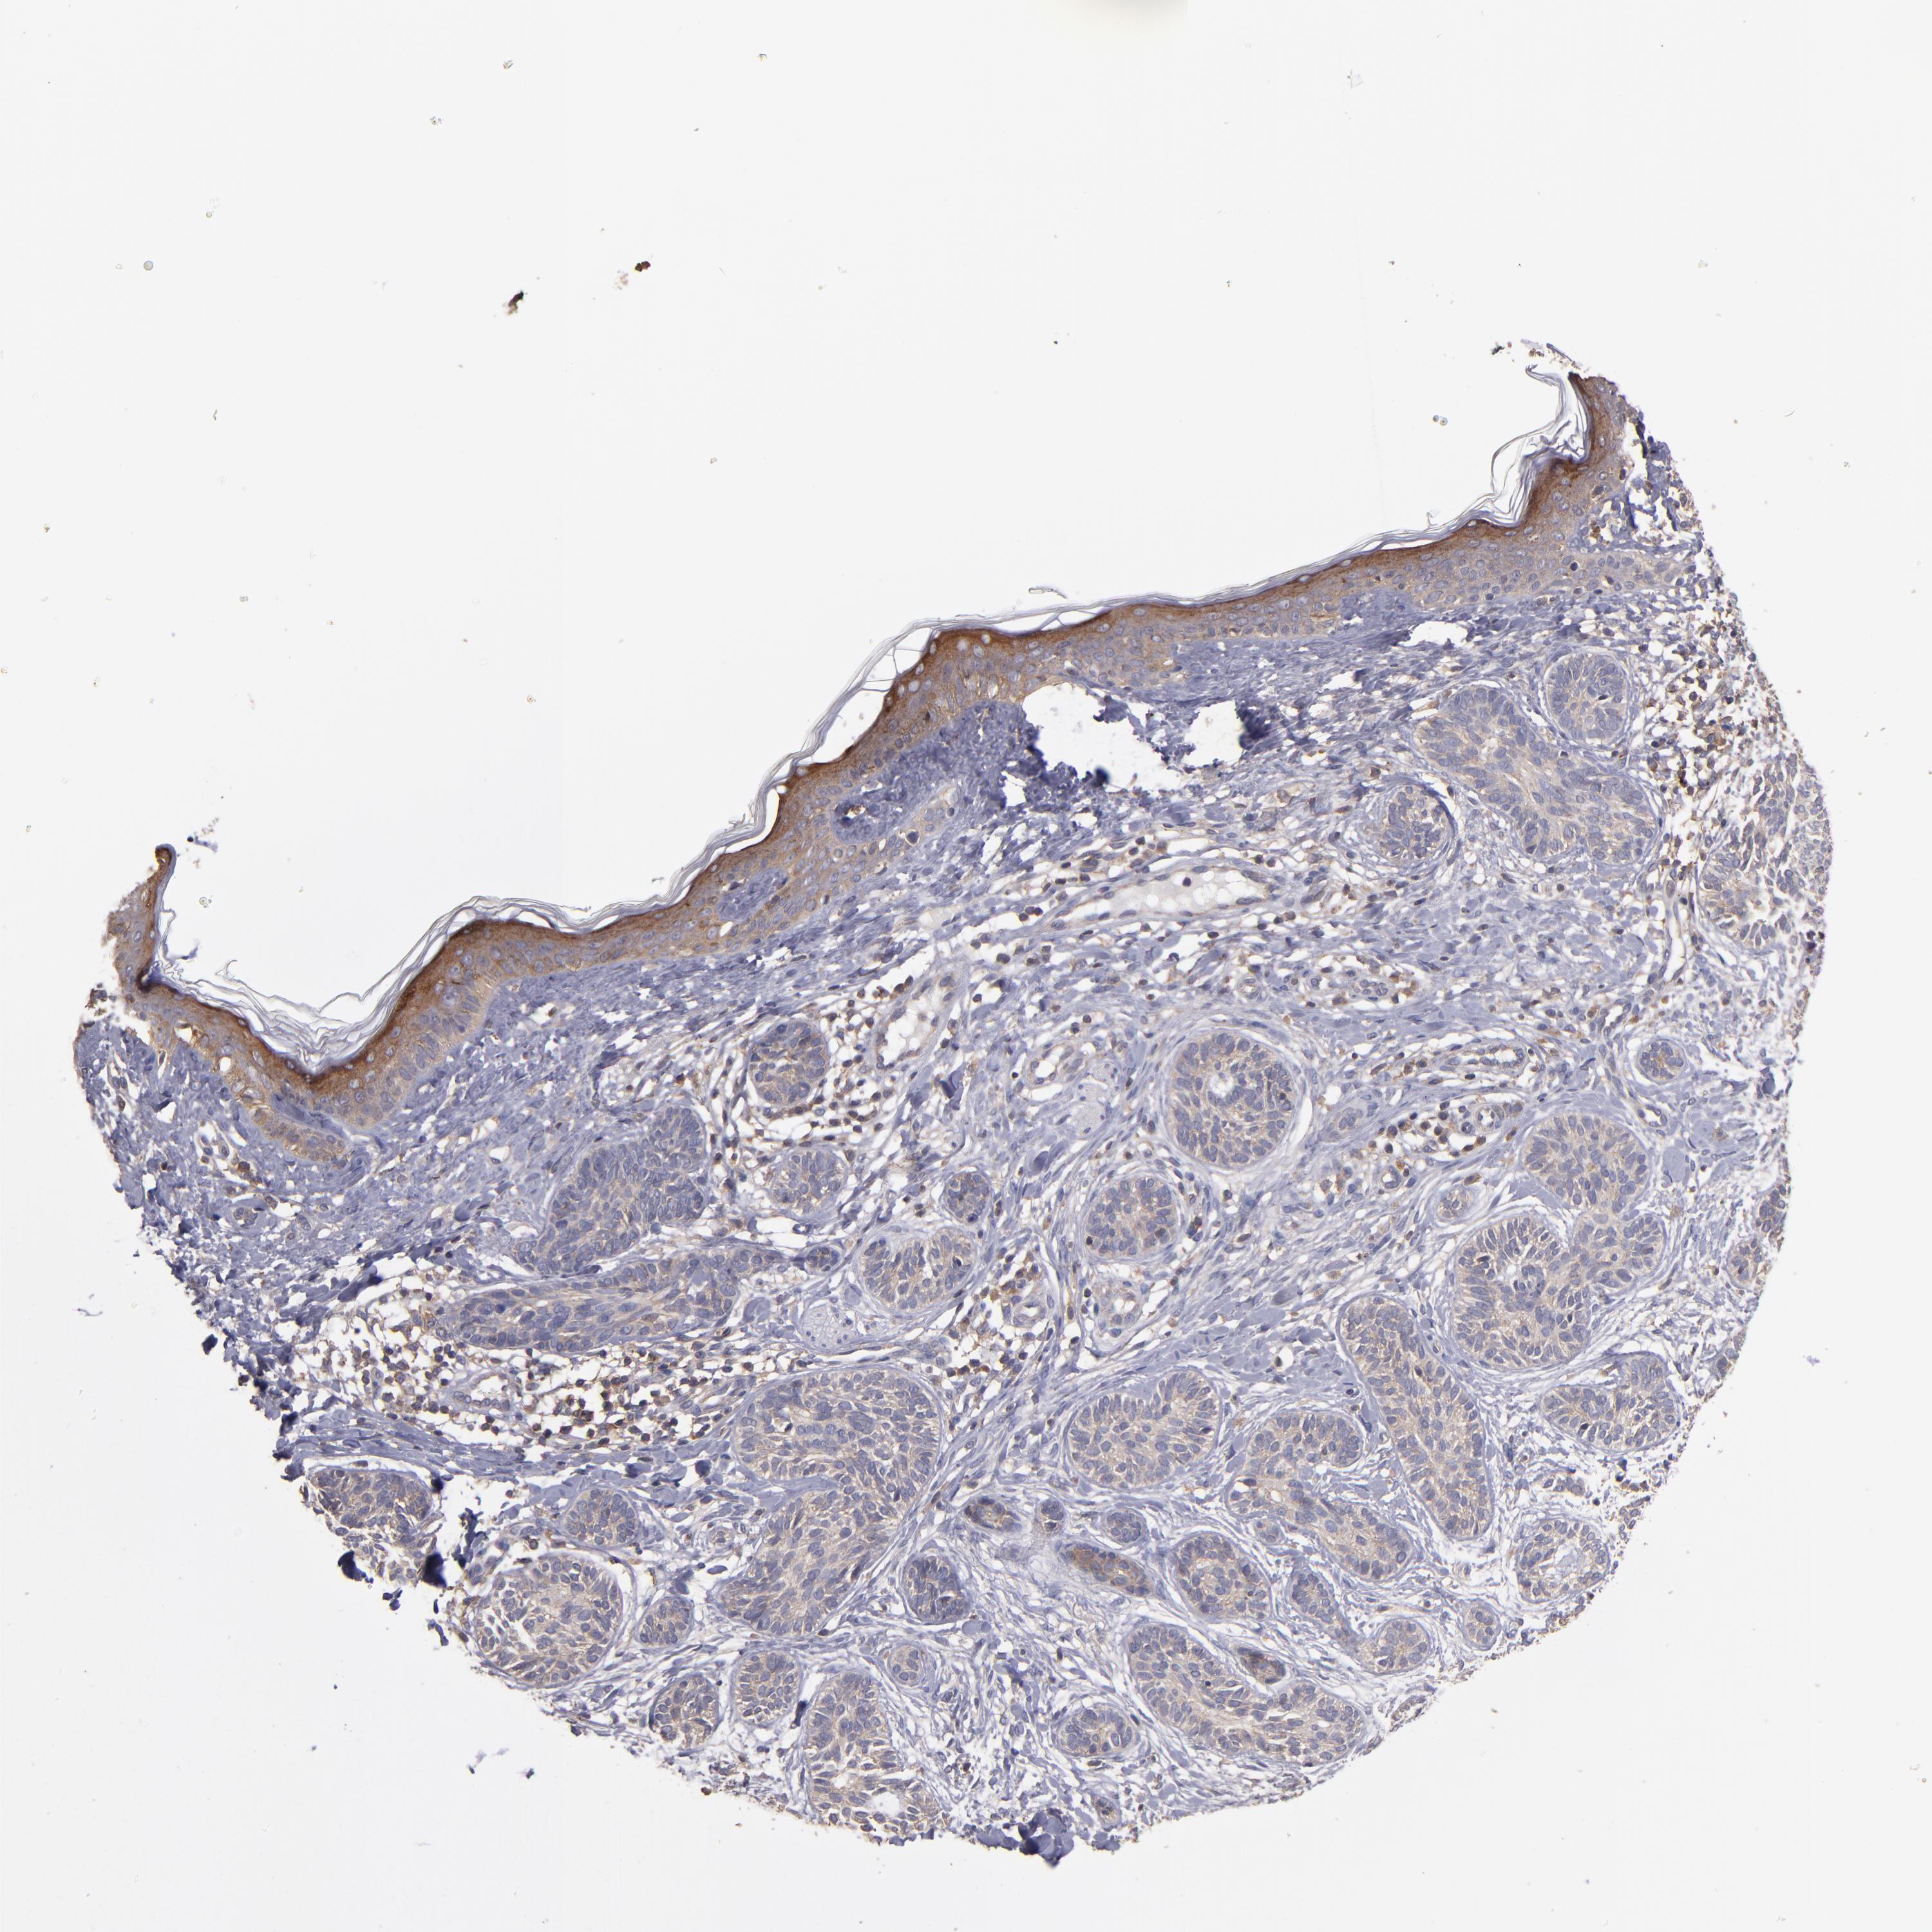

SKIN CANCER - Protein expressioni

A mouse-over function shows sample information and annotation data. Click on an image to view it in a full screen mode. Samples can be filtered based on level of antibody staining by selecting one or several of the following categories: high, medium, low and not detected. The assay and annotation is described here.

Each image is clickable and will lead to virtual microscopy that enables deeper exploration of all samples and also displays staining intensity scores, fraction scores and subcellular localization as well as patient and tissue information for each sample.

Antibody HPA003097

Papilloma, NOS